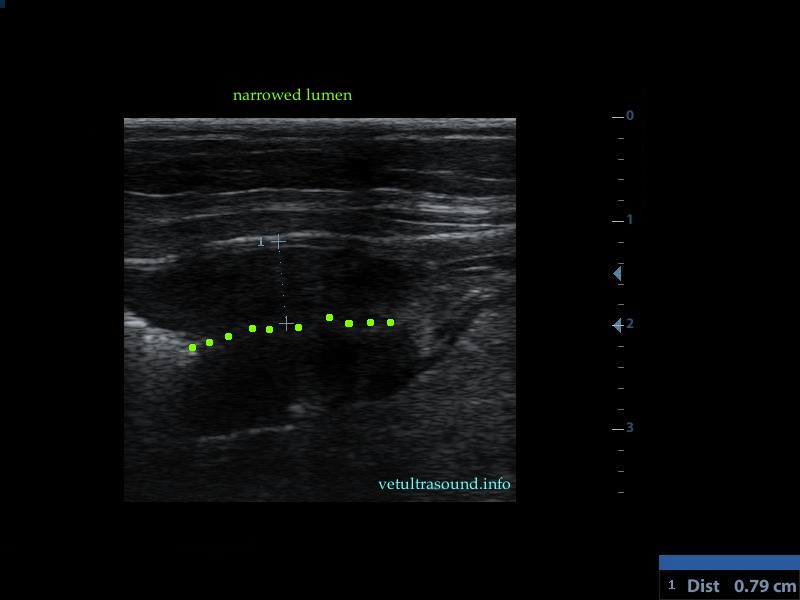

Findings: There was an increase in thickness of a segment of the small intestine, in which the normal layering was lost. This lesion extended for 3 cm(pic1). There was a restriction of the lumen, in this segment(pic2). In other parts of the ileum the muscularis propria was increased in thickness, compared to the thickness of the submucosa and the mucosa(pic3,4). The renal cortex of both kidneys was hyperechoic compared to the echogenesity of the liver and the spleen(pic5). A small amount of ascites was noted. The regional lymphnodes were enlarged and the mesenteric fat, which encircled the lesion of the small intestine, was hyperechoic.

Diagnose: These findings are compatible with alimentary tract lymphoma. There is a possibility that the kidneys are also infiltrated by lymphocytes.